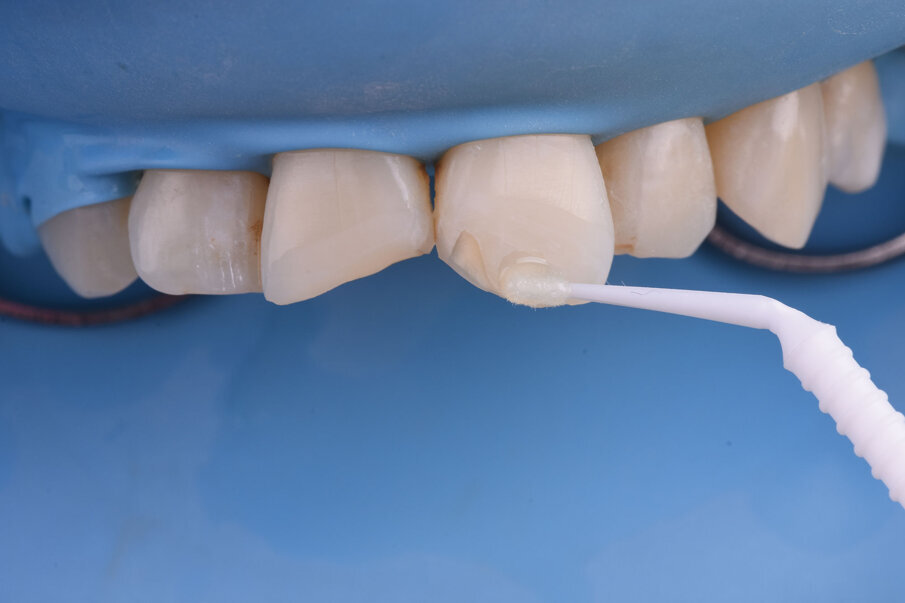

Sl. 7a: Nagrizanje ortofosfornom kiselinom, ispiranje i aplikacija adheziva (7b).

Sl. 7b: Nagrizanje ortofosfornom kiselinom, ispiranje i aplikacija adheziva (7b).